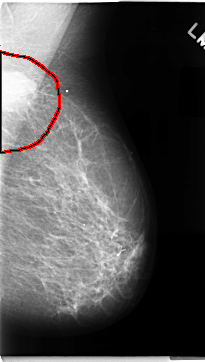

C_0072_1.RIGHT_MLO

LEFT_MLO LINES 4696 PIXELS_PER_LINE 2664 BITS_PER_PIXEL 12 RESOLUTION 50 OVERLAY

FILE: C_0072_1.LEFT_MLO.OVERLAY

TOTAL_ABNORMALITIES 1

ABNORMALITY 1

LESION_TYPE MASS SHAPE LOBULATED MARGINS MICROLOBULATED

ASSESSMENT 5

SUBTLETY 5

PATHOLOGY MALIGNANT

TOTAL_OUTLINES 1

BOUNDARY